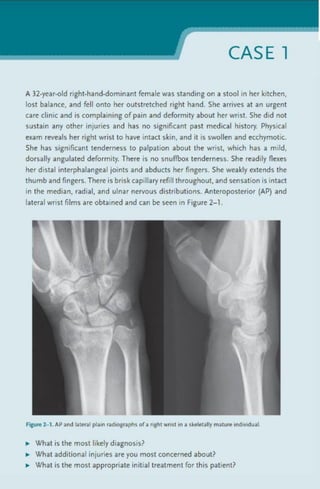

Different cases for orthopaedic surgery. For medicine, nursing, and other medical courses. Mastering the cognitive knowledge within a field such as orthopaedic surgery is a formidable task. It is even more difficult to draw on that knowledge, procure and filter through the clinical and laboratory data, develop a differential diagnosis, and finally form a rational treatment plan.